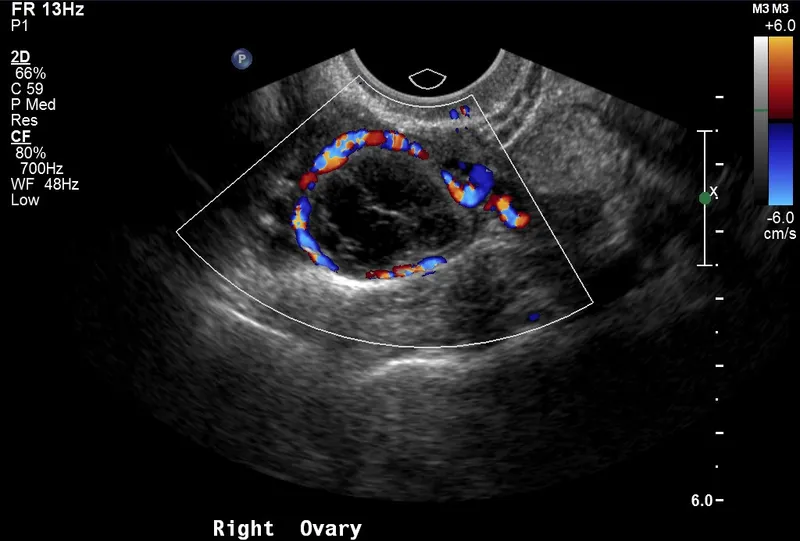

Ovulation involves coordinated proteolytic breakdown of follicular wall components. The LH surge activates matrix metalloproteinases (MMPs), particularly MMP-1 and MMP-13, which degrade collagen fibers. Simultaneously, prostaglandin E2 and F2α levels increase 5-10 fold, promoting smooth muscle contractions and inflammatory responses essential for follicle rupture.

| Ovulation Timeline | Hours Post-LH Peak | Key Events | Hormone Levels | Clinical Markers |

|---|---|---|---|---|

| Pre-surge | -12 to 0 | Estradiol peak | E2: 200-600 pg/mL | Cervical mucus changes |

| Early surge | 0-12 | LH rise begins | LH: 10-25 mIU/mL | Mittelschmerz onset |

| Peak surge | 12-24 | Maximum LH | LH: 25-40 mIU/mL | BBT nadir |

| Ovulation | 24-36 | Follicle rupture | LH declining | Progesterone rise |

| Post-ovulation | 36-48 | Corpus luteum formation | P4: 1-5 ng/mL | BBT elevation |

💡 Master This: The cumulus-oocyte complex undergoes dramatic expansion during ovulation, increasing 10-fold in volume through hyaluronic acid accumulation. This expansion enables oocyte pickup by fallopian tube fimbriae and provides the first 6-8 hours of oocyte protection post-ovulation.

The corpus luteum develops the richest blood supply per gram of any tissue, with capillary density reaching 2,000 vessels/mm³. This vascularization enables massive steroid production but also creates vulnerability to ischemic regression. Vascular endothelial growth factor (VEGF) expression increases 50-fold during luteinization, promoting angiogenesis essential for progesterone synthesis.